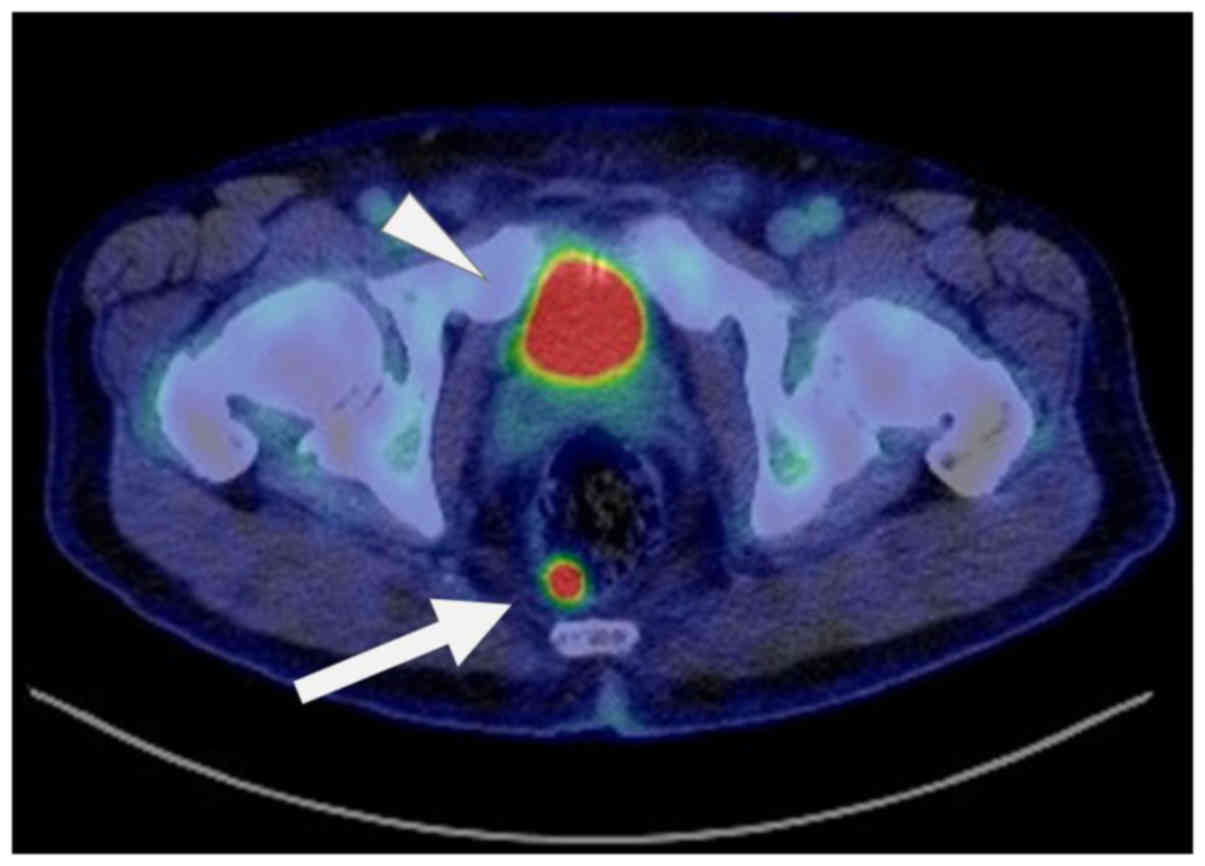

Eight months after the surgery for OS, the patient

CT scan). Follow-up third FDG-PET/CT was performed 11 months

postoperatively, and abnormal uptake was detected in the rectum

(SUVmax=14.58) (Fig. 5); on the other

hand, no other lesion identified by uptake was found in the whole

body, including the jaw, neck, bone, or lung. A colorectal tumor

Another issue is that FDG-PET should be performed

during the long-term follow-up of OS to avoid overlooking solid

SPMs. To date, the importance of detecting SPMs during follow-up

after OS treatment has not been emphasized. In our case, MDS and

diagnostic bone marrow aspiration. By contrast, no clinical

symptoms of colorectal cancer were present, and the tumor was found

incidentally by FDG-PET/CT. Recent improvements in patient survival

sites. In the present case, we could not detect the rectal lesion

by contrast-enhanced CT that was performed because local recurrence

colorectum) are relatively rare (49). In the current case, the early-stage

colorectal SPM was found incidentally by FDG-PET/CT 11 months after